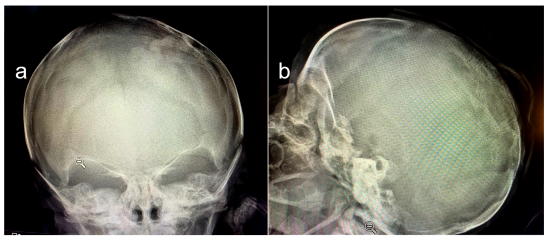

A su ingreso a Neonatología, se le realizó radiografía de cráneo, en donde se confirmó la extensión del defecto al tejido óseo subyacente con agenesia de un segmento de 1,5 × 1 cm con adelgazamiento de calota circundante (Figura 2).

Figura 2: Radiografía de cráneo frente (a) y perfil (b). Se observa ausencia de tejido óseo en zona que se corresponde con la lesión cutánea.